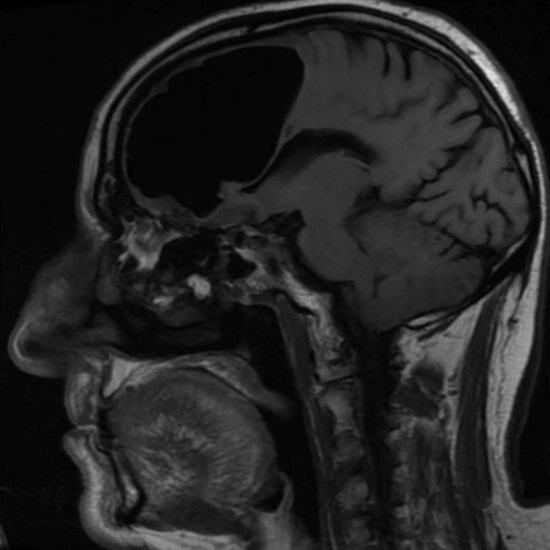

Zdravniki iz Severne Irske so bili ob pregledu presenečeni pred kratkim 84-letni bolnik, ki je k njim prišel z slabo počutjem. Po opravljenem slikanju z magnetno resonanco glave moškega zdravniki nepričakovano odkril, da mu manjka del desnega čelnega dela režnja možganov. Namesto tega je bila v lobanji upokojenca zrak žep. Potem so zdravniki ugotovili, da je dejanski fragment možganov pacient ni nikjer izginil, ampak se je mešal v smeri tega nenormalnega votlina.

Osebje bolnišnice je predlagalo, da bolnik vodi težko operacijo odstranitve zračnega žepa, vendar je moški to zavrnil od operacije. Po njegovem mnenju upokojenec za svojega starost, ponavadi se počuti zelo dobro in ne namerava svoje življenje ogrožati tako, da leži pod skalpelom. Do na srečo je kmalu dobro počutje Irca izginilo in v sedanjosti trenutek, ko ne občuti nobenega nelagodja, povezanega z njihovo nenormalno zdravstveno stanje.